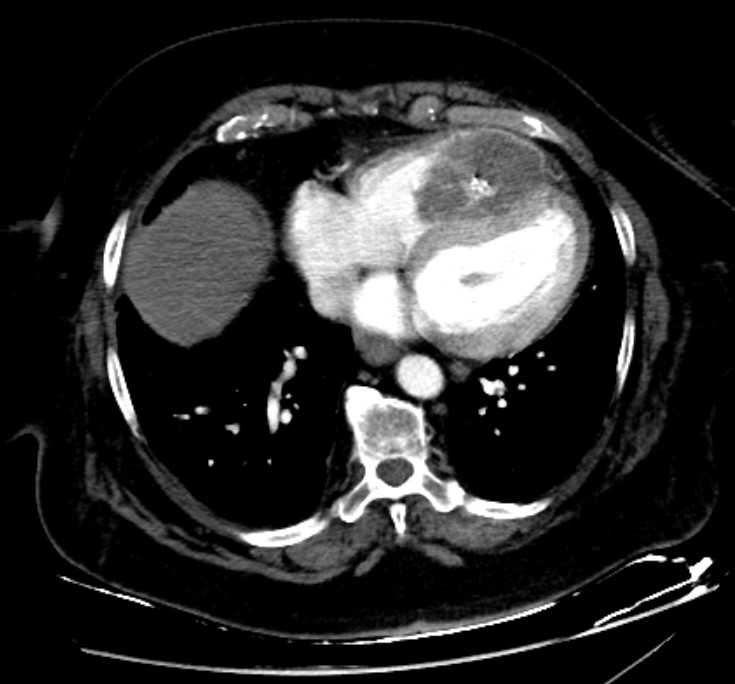

A female patient in her 60s has been followed up with annual chest-abdominopelvic computed tomography (CT) due to a clinical history of extraskeletal mesenchymal chondrosarcoma with disseminated metastatic disease. She was previously submitted to various surgical treatments, namely excision of the primary lesion located on the left thigh thirteen years before, as well as bilateral pulmonary and colic metastasectomy, left adrenalectomy and nephrectomy, splenectomy and caudal pancreatectomy in 2019. In a routine contrast-enhanced thoraco-abdominopelvic CT, a round, solid mass was found with heterogeneous attenuation, as well as internal calcifications, occupying most of the right ventricular chamber, due to heart metastasis from extraskeletal mesenchymal chondrosarcoma. It involves the right apex and almost two thirds of the ventricular septum, causing discrete bulging to the left.(Figs. 1, 2 and 3)

Figure 1: Axial contrast-enhanced CT image reveals a round, solid mass, with heterogeneous attenuation, as well as internal calcifications, occupying most of the right ventricular chamber, due to heart metastasis from extraskeletal mesenchymal chondrosarcoma. It involves the right apex and almost two thirds of the ventricular septum, causing discrete bulging to the left.